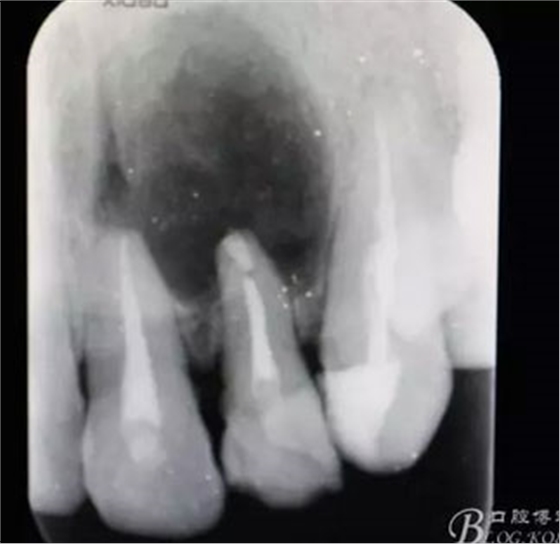

圖1.術(shù)前患者的x光根尖片檢查影像:22根尖完全位于囊腔內(nèi),牙槽骨吸收至嵴頂約5mm。22松動(dòng)Ⅰ度。

圖20.術(shù)后的根尖片:22根尖MTA倒充填、21根尖切除術(shù)。